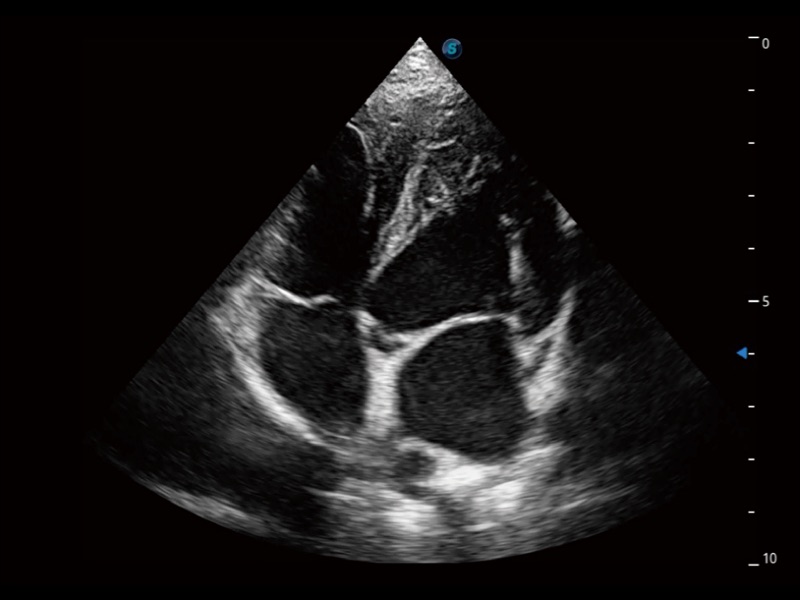

通过360度任意调节3条M型取样线,在同一心动周期上观察心脏不同位置的运动曲线,得到准确的心功能测量数据,有效评估心肌运动及左心室功能。